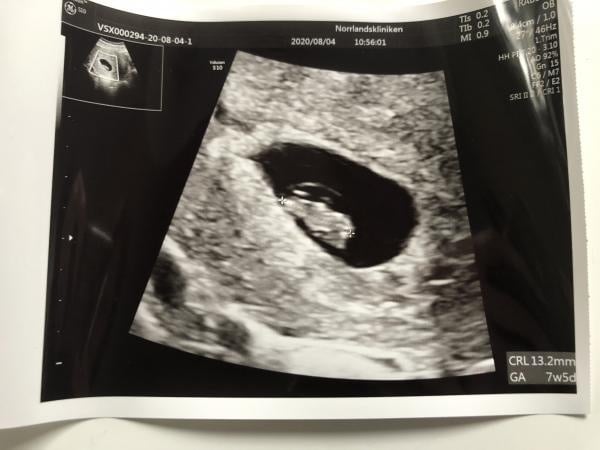

Ja de går väldigt snabbt! Längtar dock till första ultraljudet den 4e augusti, så man ser att det verkligen är något där inne.. tog ett digitalt test imorse som visade 3+ så det kändes bra iaf! Varit lite orolig då jag inte haft lika ömma bröst som tidigare.

Det går bra här, går in i v.8 imorgon! Har tidigt ultraljud på tisdag så både längtar och är jättenervös. Väldigt uppsvälld mage som gör lite ont!

Uppdatering, allt såg jättefint ut idag på ul med tickande hjärta! Så häftigt!! Nu hejar jag på er som en kvar <3